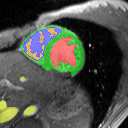

Heart Segmentation:

In this setting we only used color models for the data term and no shape priors. Figure 17(a) shows the labels tree. For a-exp to escape its local minimum it needs to first expand the left ventricle and then the left papillary muscles. However, expanding on left ventricle would lead to a higher energy than the current one. Path-Moves avoids this local minimum by allowing both labels to expand simultaneously when performing a Path-Move on the left papillary muscles.

| (a) tree | |

![]() |

| (b) ground truth | (c) ours (Path-Moves) |